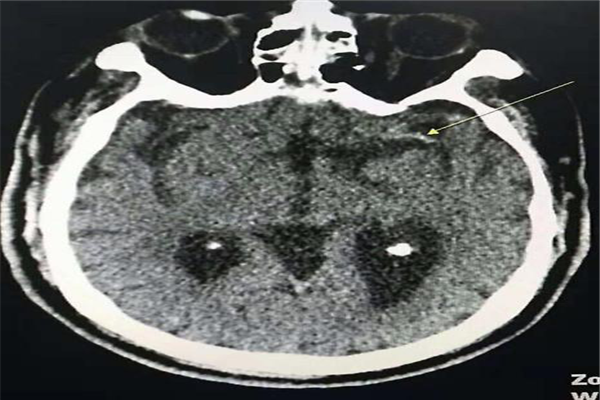

患者江某在家中,于凌晨出現(xiàn)意識(shí)不清,不能言語(yǔ),右側(cè)肢體活動(dòng)不靈癥狀,患者老伴在晨起后發(fā)現(xiàn)情況不對(duì),遂立即將他送往西電集團(tuán)醫(yī)院?;颊呷朐簳r(shí)已經(jīng)呈淺昏迷狀,接診的神經(jīng)外科馮磊副主任醫(yī)師迅速對(duì)老人進(jìn)行了查體,發(fā)現(xiàn)他雙側(cè)瞳孔對(duì)光反射遲鈍,右側(cè)肢體肌力0級(jí)、巴氏征陽(yáng)性。馮磊副主任醫(yī)師立即安排老人進(jìn)行CT檢查, CT檢查報(bào)告所示:左側(cè)大腦半球皮層腦溝變淺;左外側(cè)裂可見(jiàn)高密度影。老人被診斷為急性腦梗塞;左側(cè)大腦中動(dòng)脈急性閉塞;NIHSS評(píng)分20分。馮磊副主任醫(yī)師立刻向神經(jīng)外科林濤科主任匯報(bào)了患者病情,林濤主任果斷安排,迅速組織卒中中心相關(guān)人員討論患者病情,制訂詳盡的治療方案。在經(jīng)過(guò)卒中中心侯沛紅主任的指導(dǎo)建議,林濤主任、馮磊副主任醫(yī)師及相關(guān)人員討論,針對(duì)當(dāng)前患者尚在機(jī)械取栓時(shí)間窗(發(fā)病6h內(nèi)),建議患者家屬應(yīng)立即進(jìn)行手術(shù),才有搶救治愈的希望和可能??墒牵?dāng)與家屬談話(huà)溝通后,家屬顧慮手術(shù)風(fēng)險(xiǎn),且患者年紀(jì)較大,猶豫不定、遲遲不能決定是否手術(shù)......